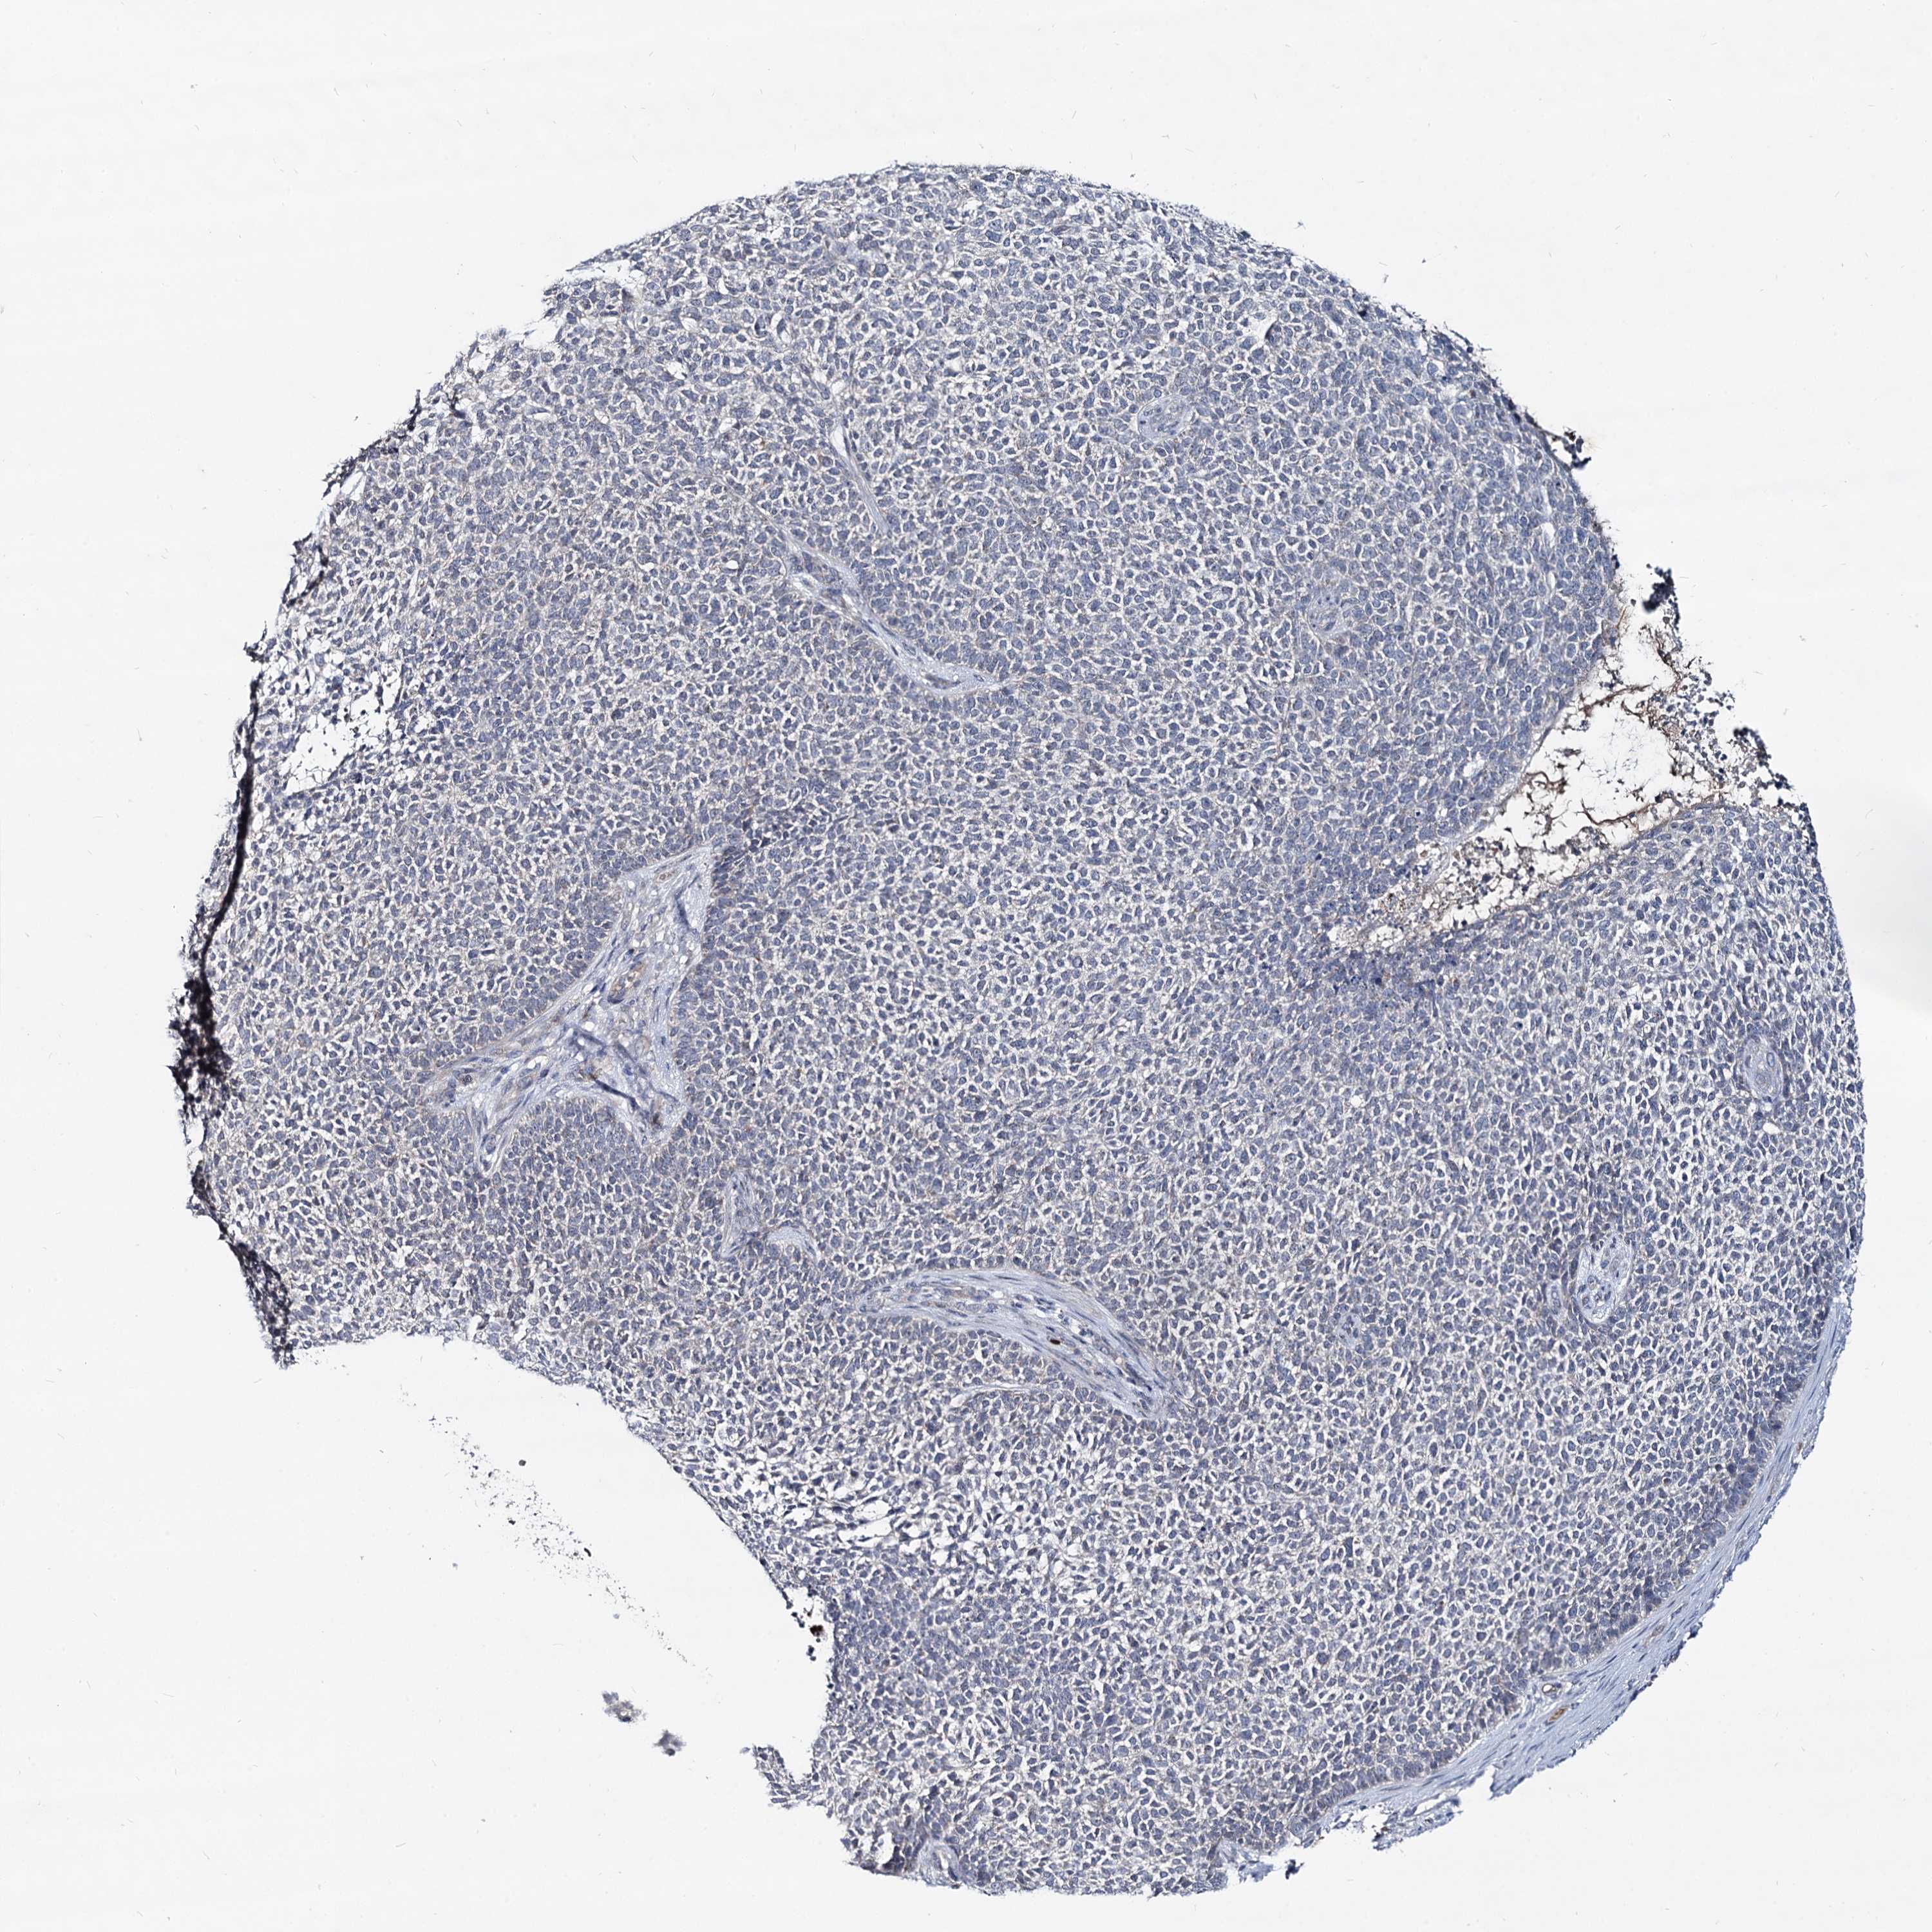

SKIN CANCER - Protein expressioni

A mouse-over function shows sample information and annotation data. Click on an image to view it in a full screen mode. Samples can be filtered based on level of antibody staining by selecting one or several of the following categories: high, medium, low and not detected. The assay and annotation is described here.

Each image is clickable and will lead to virtual microscopy that enables deeper exploration of all samples and also displays staining intensity scores, fraction scores and subcellular localization as well as patient and tissue information for each sample.

Antibody HPA039343

Basal cell carcinoma